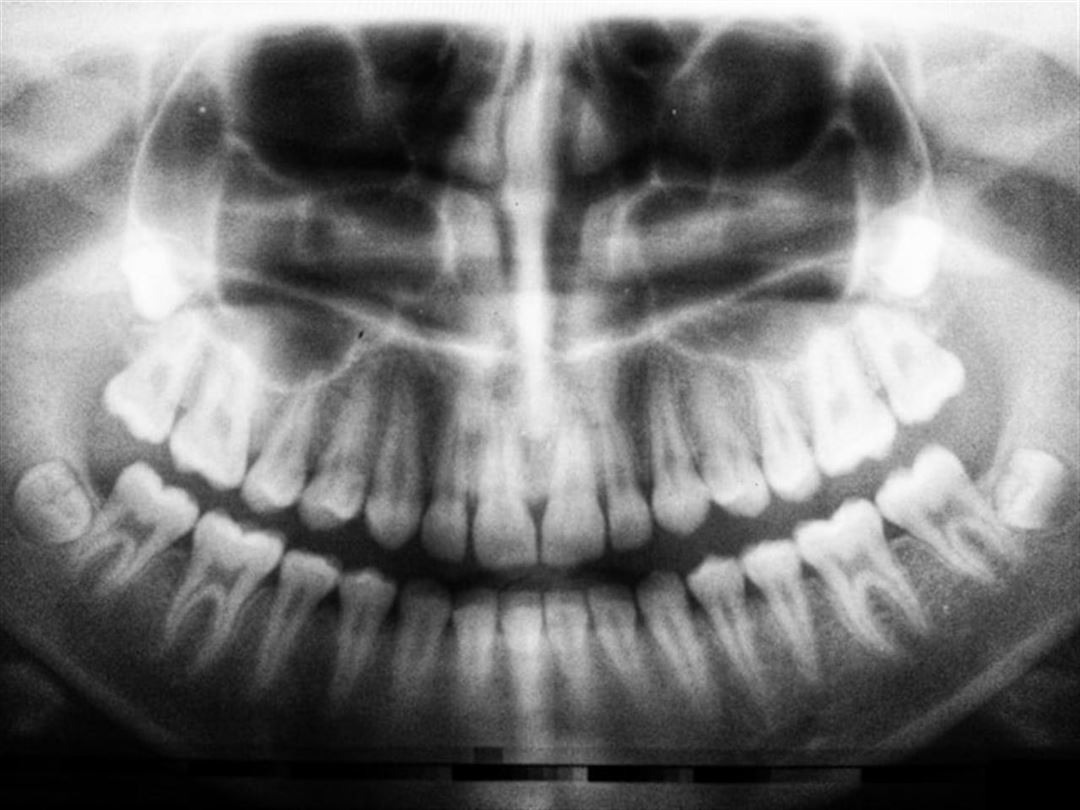

Forebyggelse er nøglen til at bevare sundheden for en visdomstand. Regelmæssige tandlægebesøg og røntgenbilleder kan hjælpe med at opdage eventuelle problemer tidligt og planlægge passende behandlinger. Desuden er god mundhygiejne afgørende for at forhindre karies og tandkødsproblemer omkring visdomstænderne.